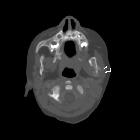

Wilms tumoru

with bony-mandibular, rib and calvarial metastases. Lytic lesion in left mandibular ramus with periosteal reaction.